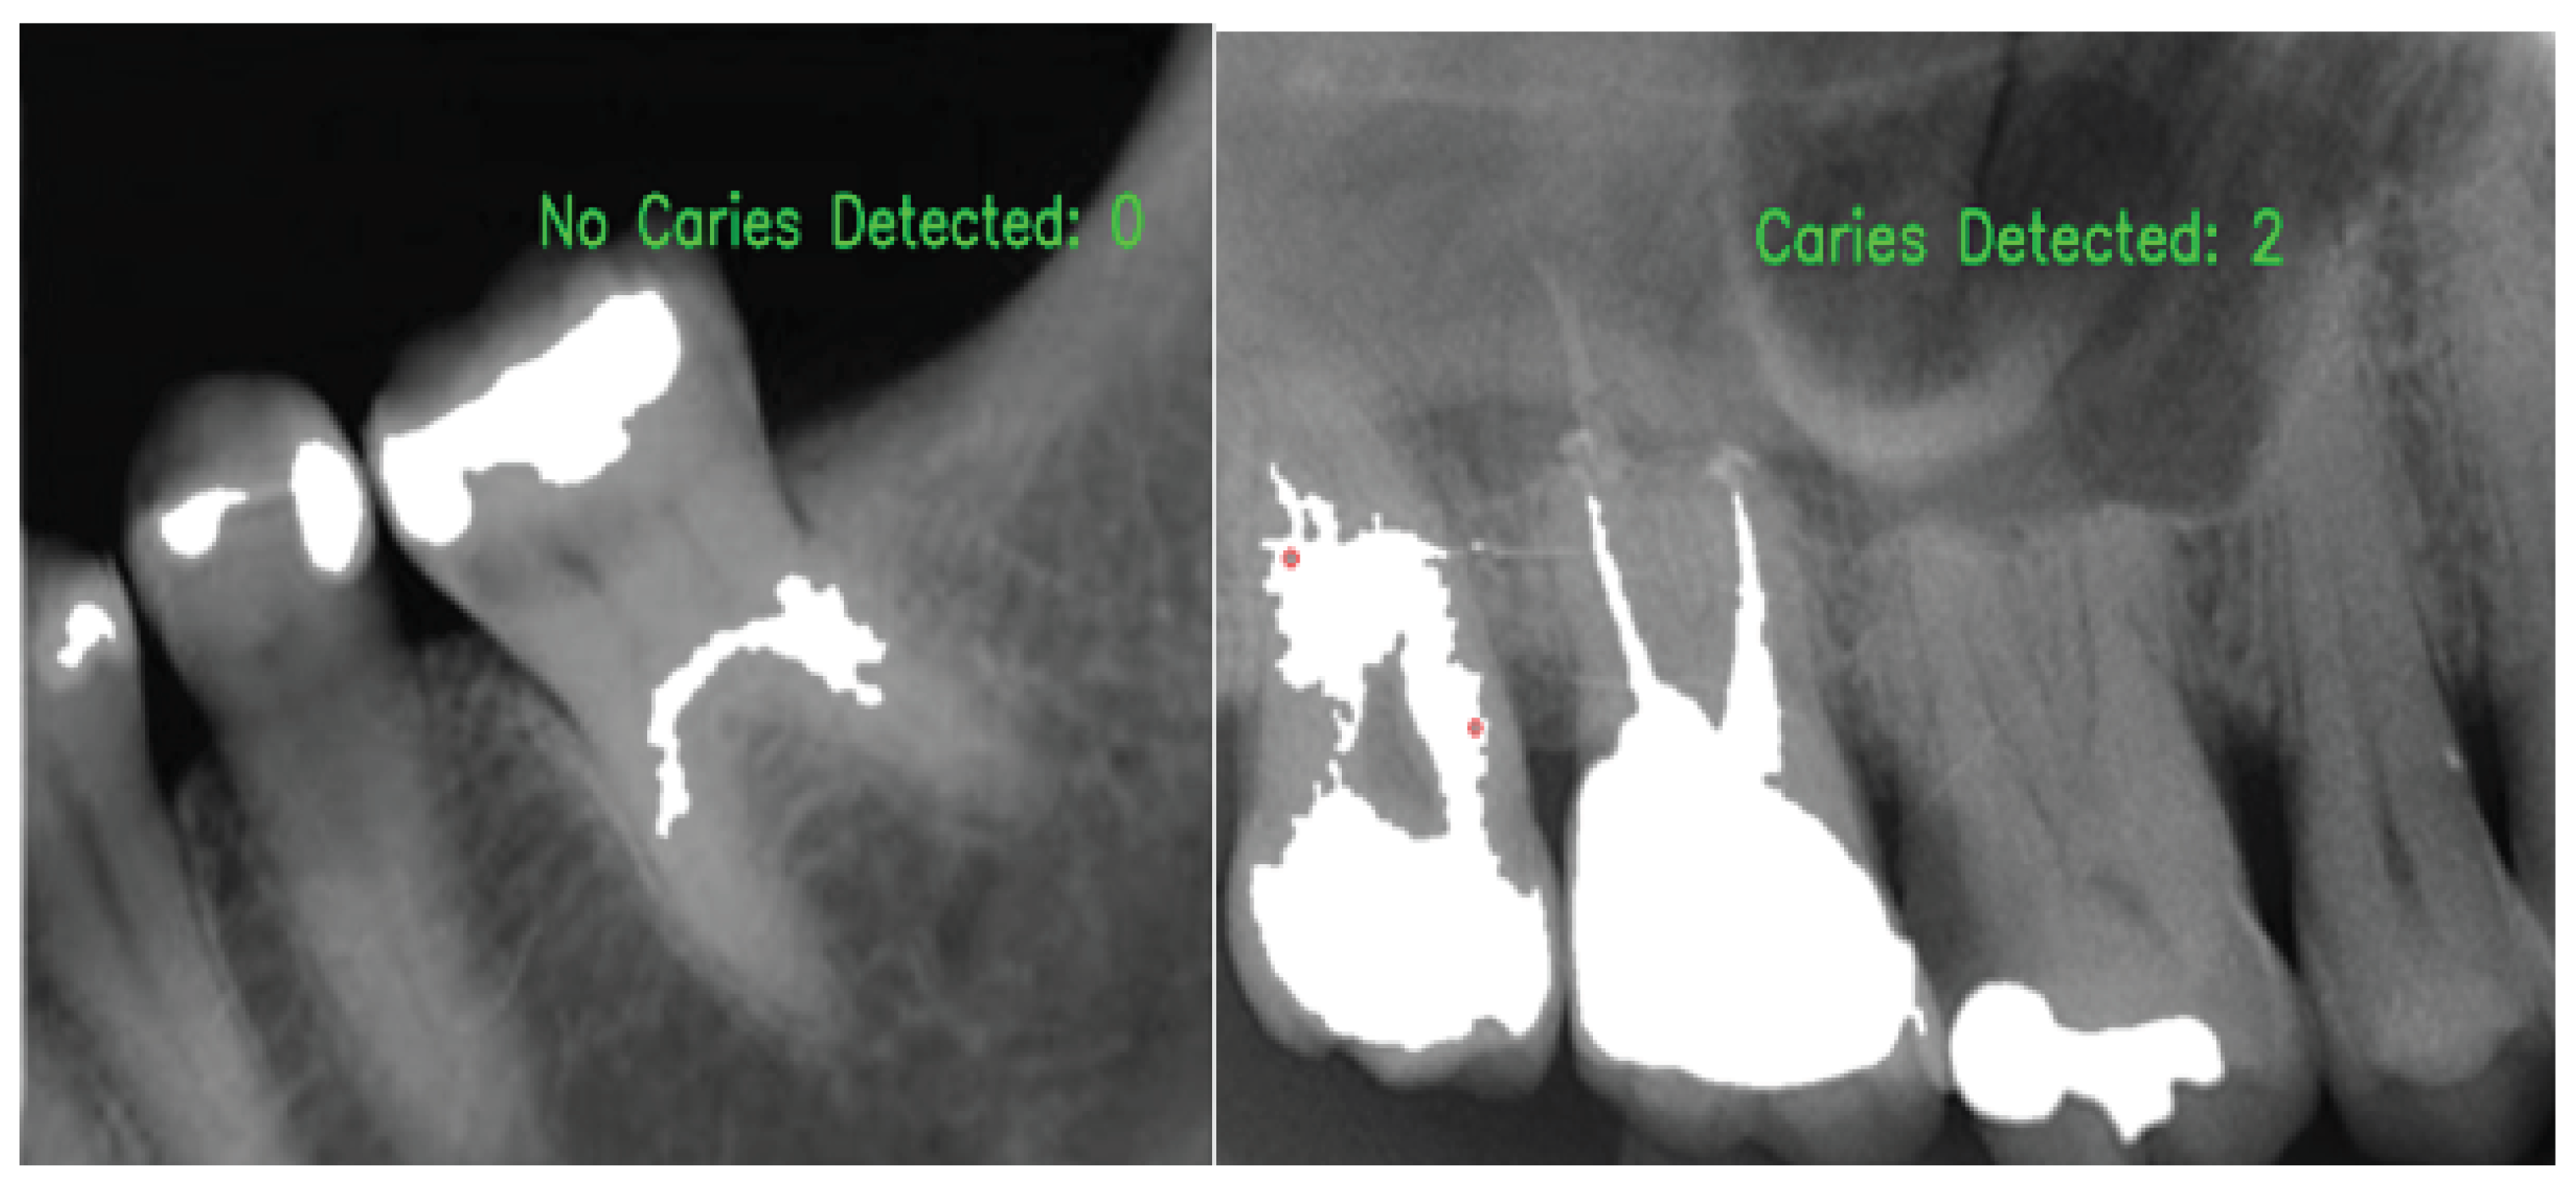

2.3.2. Caries Candidate Detection

2.3.3. Caries Candidate Selection